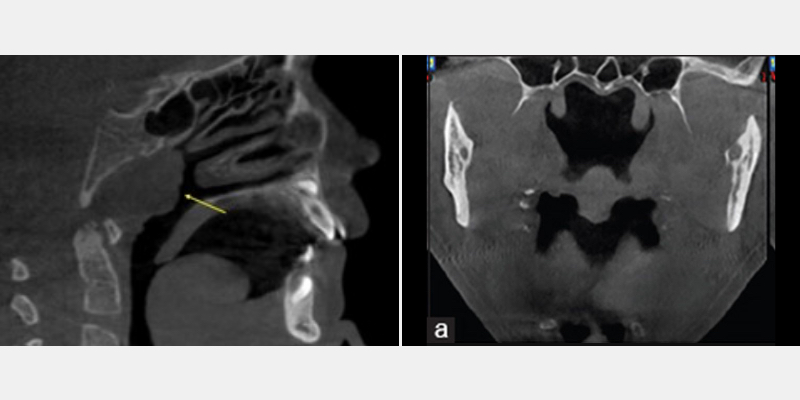

Tonsils and Adenoids

A CBCT can also indicate the presence or absence of enlarged tonsils and adenoids (Fig. 5). These anatomic structures in the parapharyngeal region can impact a patient’s health and sleep by narrowing, restricting, or blocking the airway.

When evaluating patients and their sleep disorders, the “why,” or the etiology, is critical when offering solutions and/or treatment options. This is especially true with children, as early intervention can prevent and improve the quality of their growth and development.